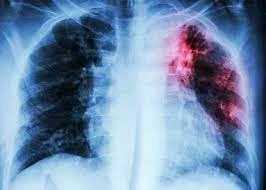

อาการที่ปรากฎให้เห็นได้ชัดเจน ได้แก่

1. ไอติดต่อกันเกิน 2 สัปดาห์ อาจเป็นได้ทั้งแบบไอแห้งๆ ไอมีเสมหะ หรือไอมีเสมหะปนเลือด

2. มีไข้ต่ำๆ ช่วงบ่ายหรือค่ำ

3. เบื่ออาหาร น้ำหนักลดลงผิดปกติ

4. เหงื่อออกมากผิดปกติช่วงกลางคืน

5. เจ็บหน้าอก เหนื่อยหอบ